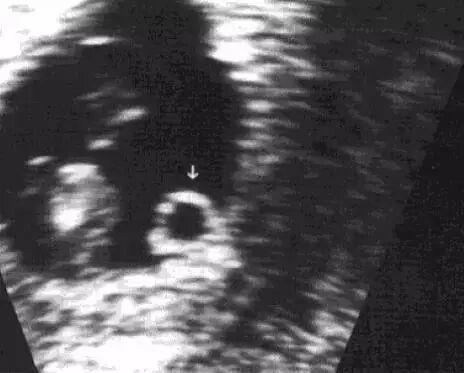

经阴道超声最早6周,经腹超声最早7周可以见到胚芽及胎心搏动。胚芽径线在2mm时候常能见到原始心管的搏动,B超中表现为卵黄囊一侧的增厚部分。出现胎心搏动可确定为活胎。

妊娠6周,胚芽贴附在卵黄囊上